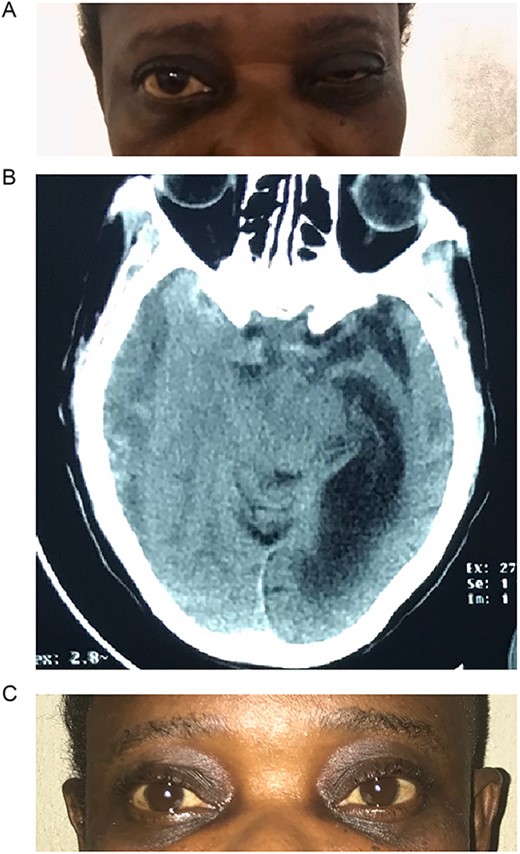

Case 2 – paraplegia

A 72-year-old man who was admitted by the orthopaedic team on account of progressive lower extremity weakness of 3 weeks duration that culminated in his inability to ambulate independently. He had no other neurologic symptoms. He denied history of prior trauma. Although he was a known hypertensive, he had not been on antiplatelets. His neurologic examination revealed a fully conscious elderly man who was awake, alert, well oriented in time, place, and person. Other neurologic examination findings were normal except for grade 2 power in both lower limbs. His deep tendon reflexes were normal in all extremities. Sensory function was intact.

Prior to this, he had been managed for low back pain and lumbar spondylosis. Spine MRI done prior to neurosurgery consultation did not explain the lower extremity motor weakness. Brain CT done revealed bilateral fronto-parietal CSDH (Fig. 2A). He was worked up for urgent surgical evacuation through a bilateral frontal and parietal burr hole drainage. He made good neurologic improvement and his lower extremity power returned to normal on the 8th day post op. Post-operative CT scan done at 4 weeks follow-up showed satisfactory resolution of the haematoma (Fig. 2B).

(A) Pre-op showing bilateral CSDH. (B) Post op complete resolution of CSDH.

Another unusual presentation was paraparesis in a 72-year-old man. With a long-standing history of low back pain and lumbar spondylosis, an initial diagnosis of degenerative spine disease was considered. However, with an unremarkable spine MRI, a brain CT was done and it revealed a bilateral CSDH with extension into the anterior inter-hemispheric fissure. We postulated that the bilateral motor involvement of the lower extremity could be from two possibilities.

The first possibility was a direct compression of the lower limb motor strip against the falx cerebri from the bilateral subdural collection like what is seen in a parasagittal meningioma [13].

Second, subfalcine herniation could result in the compression of the branches of the anterior cerebral artery with resultant ischaemia of the medial surfaces of the frontal lobes, which bears the motor homunculus of the lower extremities. Koyama et al. [13] demonstrated a vascular aetiology in case of interhemispheric SDH causing paraparesis. In their patient who had left hemiparesis and right interhemispheric SDH, an angiography demonstrated a lateral displacement of the right callosomarginal artery and an avascular area between the falx and the callosomarginal artery. Our patient made a dramatic clinical improvement once the haematoma was drained and was functionally independent within 1 week after surgery.